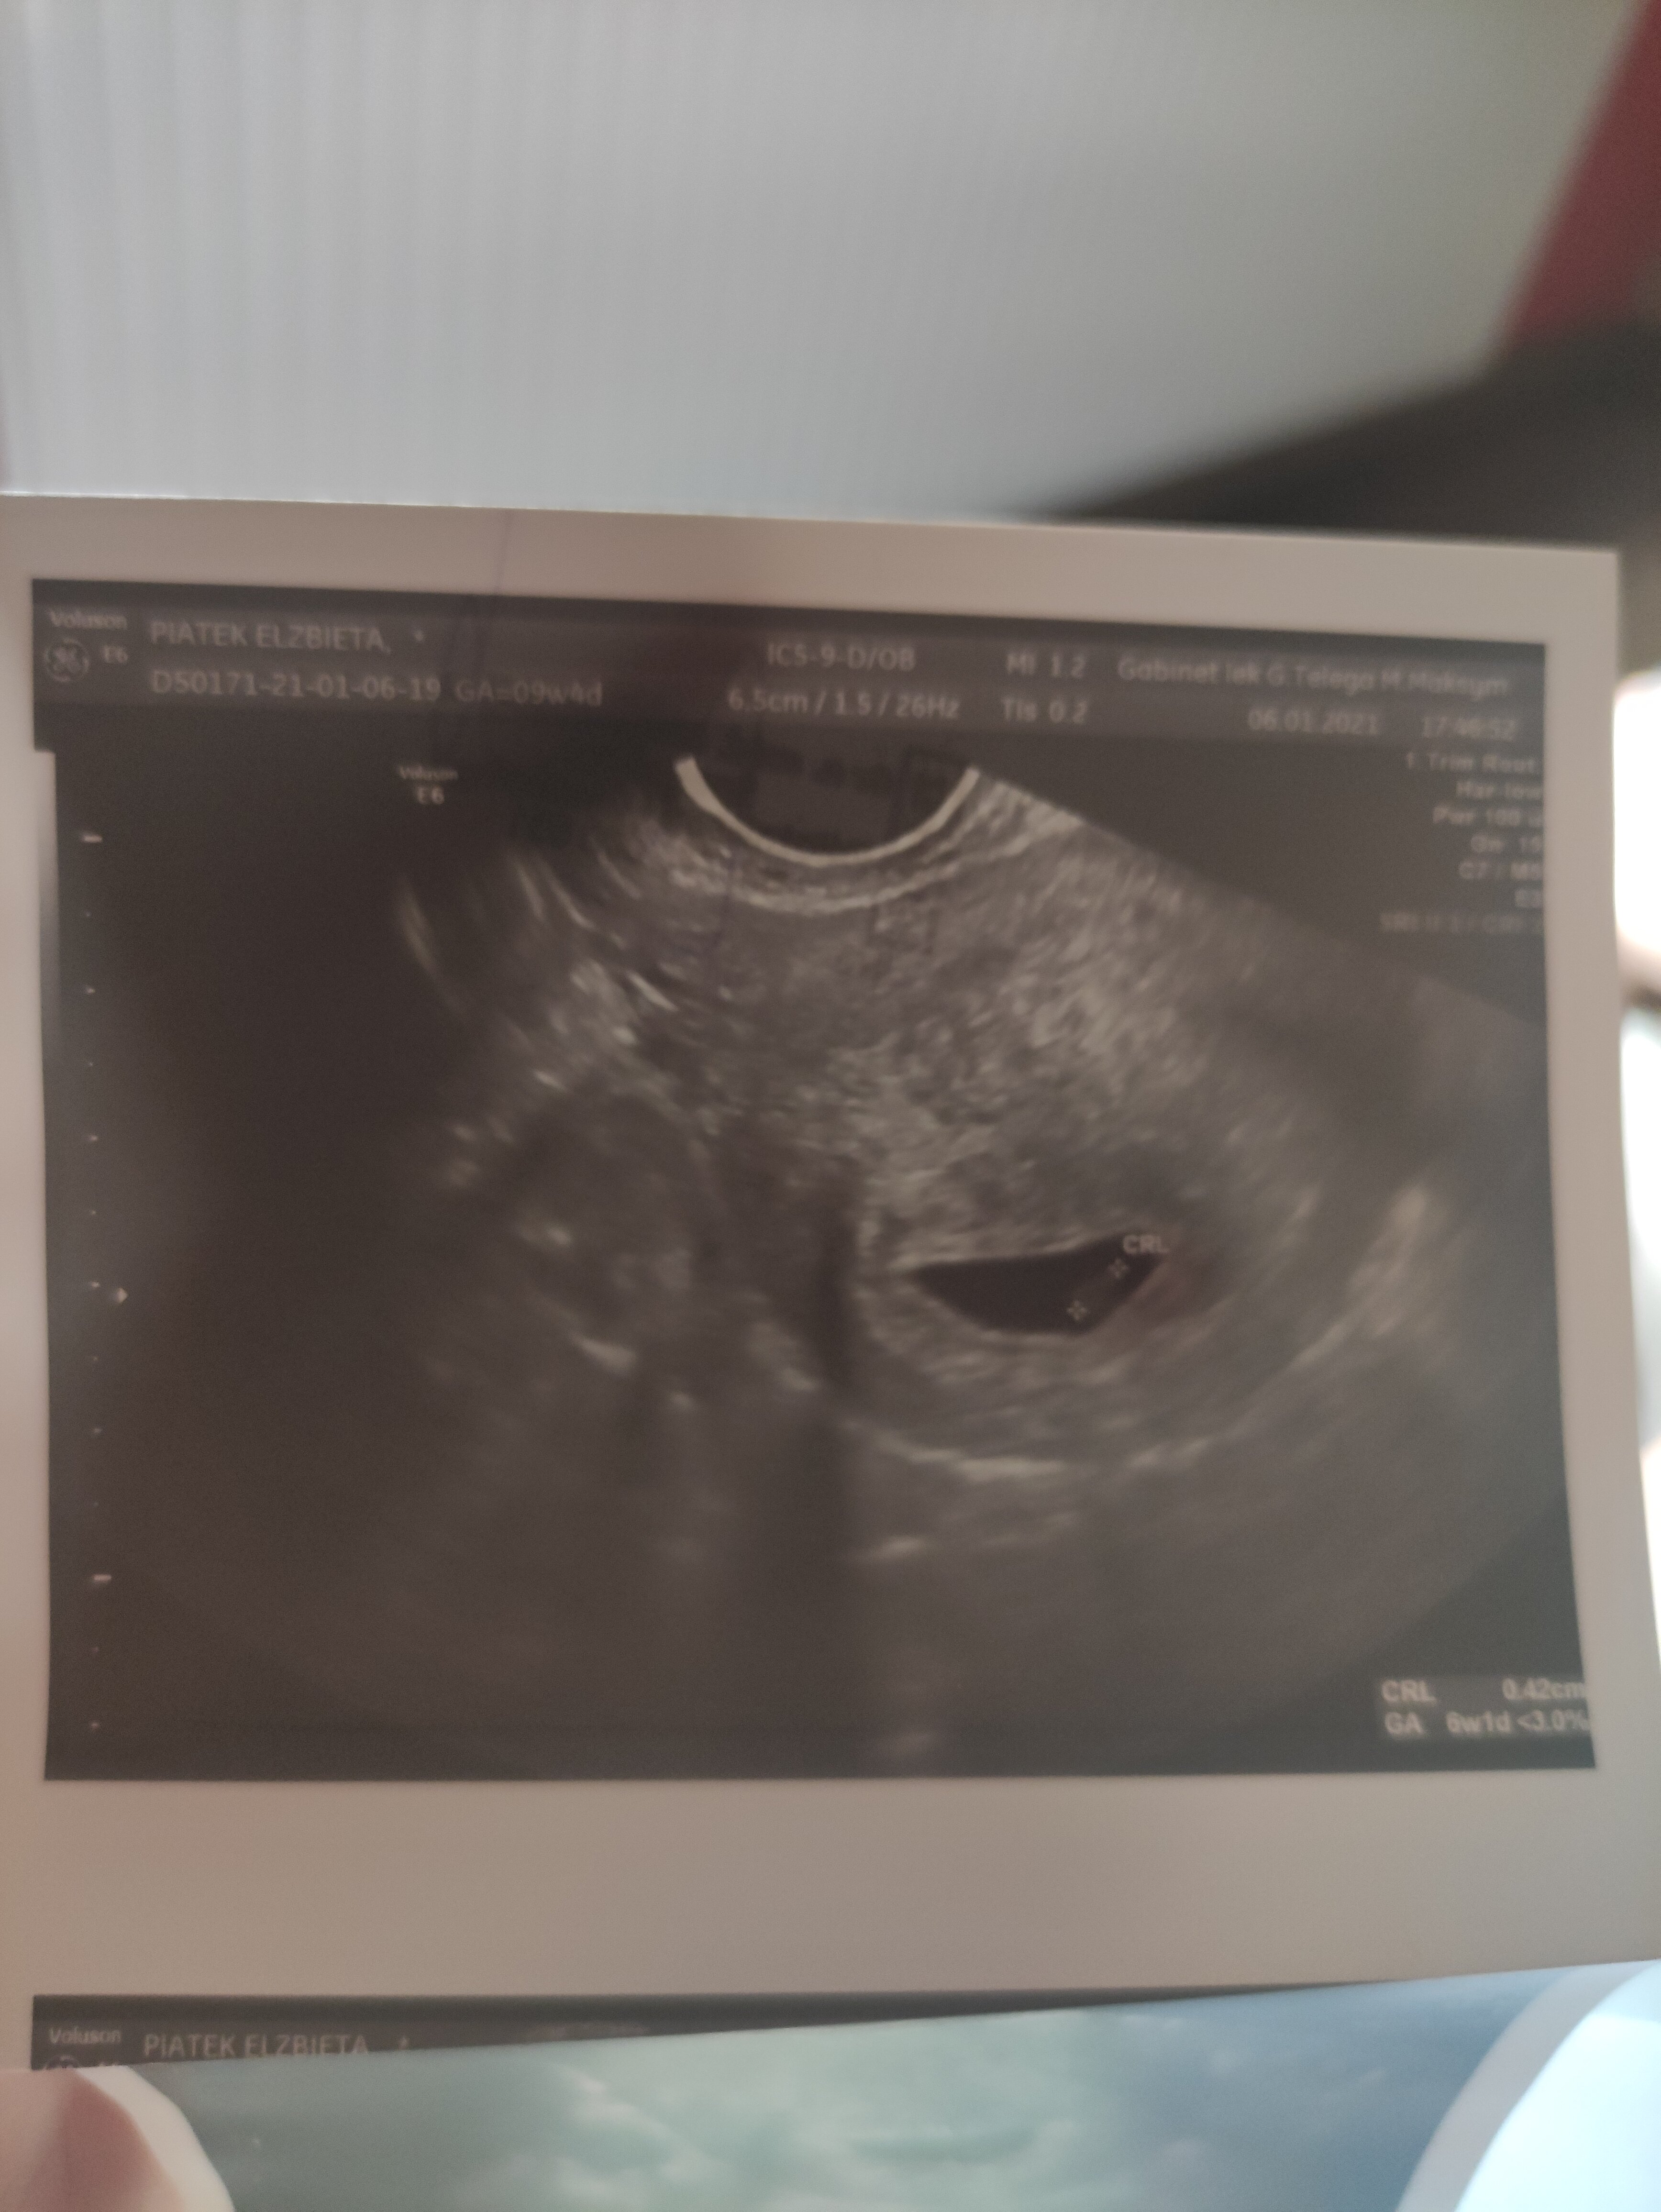

To moje USG z drugiej ciazy te pierwsze podejrzenie pustego jaja a drugie pojawienie się zarodka ale bez bicia

Załączniki

• IMG_20210611_111819.jpg

IMG_20210611_111819.jpg

1,6 MB · Wyświetleń: 169

• IMG_20210611_111908.jpg

IMG_20210611_111908.jpg

1,5 MB · Wyświetleń: 160